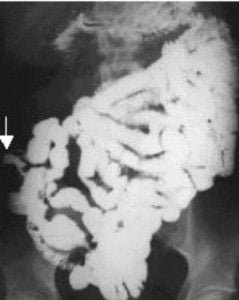

Abdomen, aparato digestivo y via biliarTécnicas de Exploración Radiológica Tránsito del intestino delgado Parte II 28 junio, 2012 Tidito Transito intestinal contraste simple Transito intestinal doble contraste yeyuno e ileon Patologia de Transito intestinal – Enfermedad celiaca Tumor maligno ileon terminalEnfermedad inflamatoria intestinal